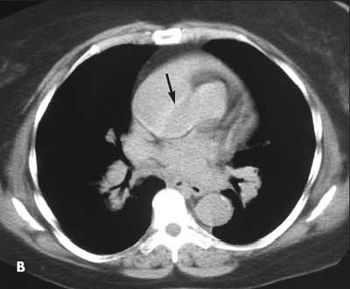

Lofgren syndrome, lumbar disk herniation, suppurative appendicitis with rupture, rotator cuff impingement syndrome, aortic dissection.

Cardiovascular diseases here are patent foramen ovale, interatrial septal aneurysm, myocarditis, aoritis, internal carotid artery dissection, heart-hand syndrome.